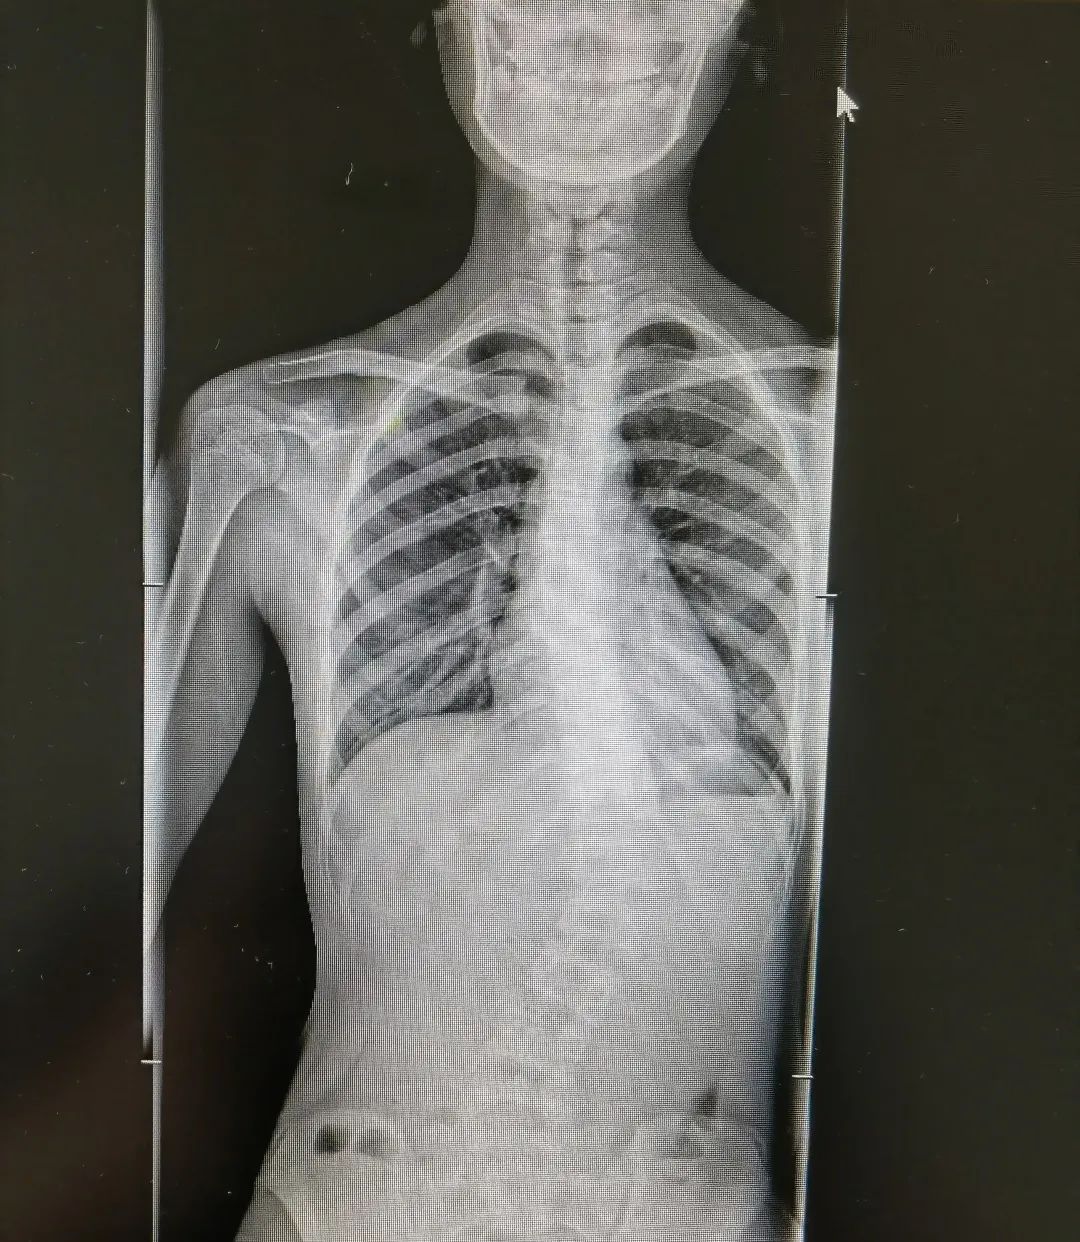

青少年特发性脊柱侧弯术前术后图

暑假,骨科病房里和梦梦一样的孩子还有7个,都是因为严重的青少年特发性脊柱侧弯陆续入院。

“在所有脊柱侧弯类型中,临床中占比最高、最常见的就是青少年特发性脊柱侧弯,约占脊柱侧弯的百分之70%。目前它的发病原因尚不清楚,可能与遗传、免疫、激素、姿势不良等因素有关,往往从10岁左右开始发病。根据严重程度不同,治疗方案也有差异。部分患儿可以采用支具矫形、物理康复锻炼等方式进行保守治疗,但是如果侧弯度数大于40°,就需要考虑手术矫形。”

陈文昊副主任表示,虽然青少年特发性脊柱侧弯目前病因不明,但部分患有青少年特发性脊柱侧弯的孩子都有一个特点——短时间内长得都比较快。青春期骨骼快速生长发育,原本轻微的脊柱侧弯此时也会迅速进展,一年甚至可长歪10度以上。